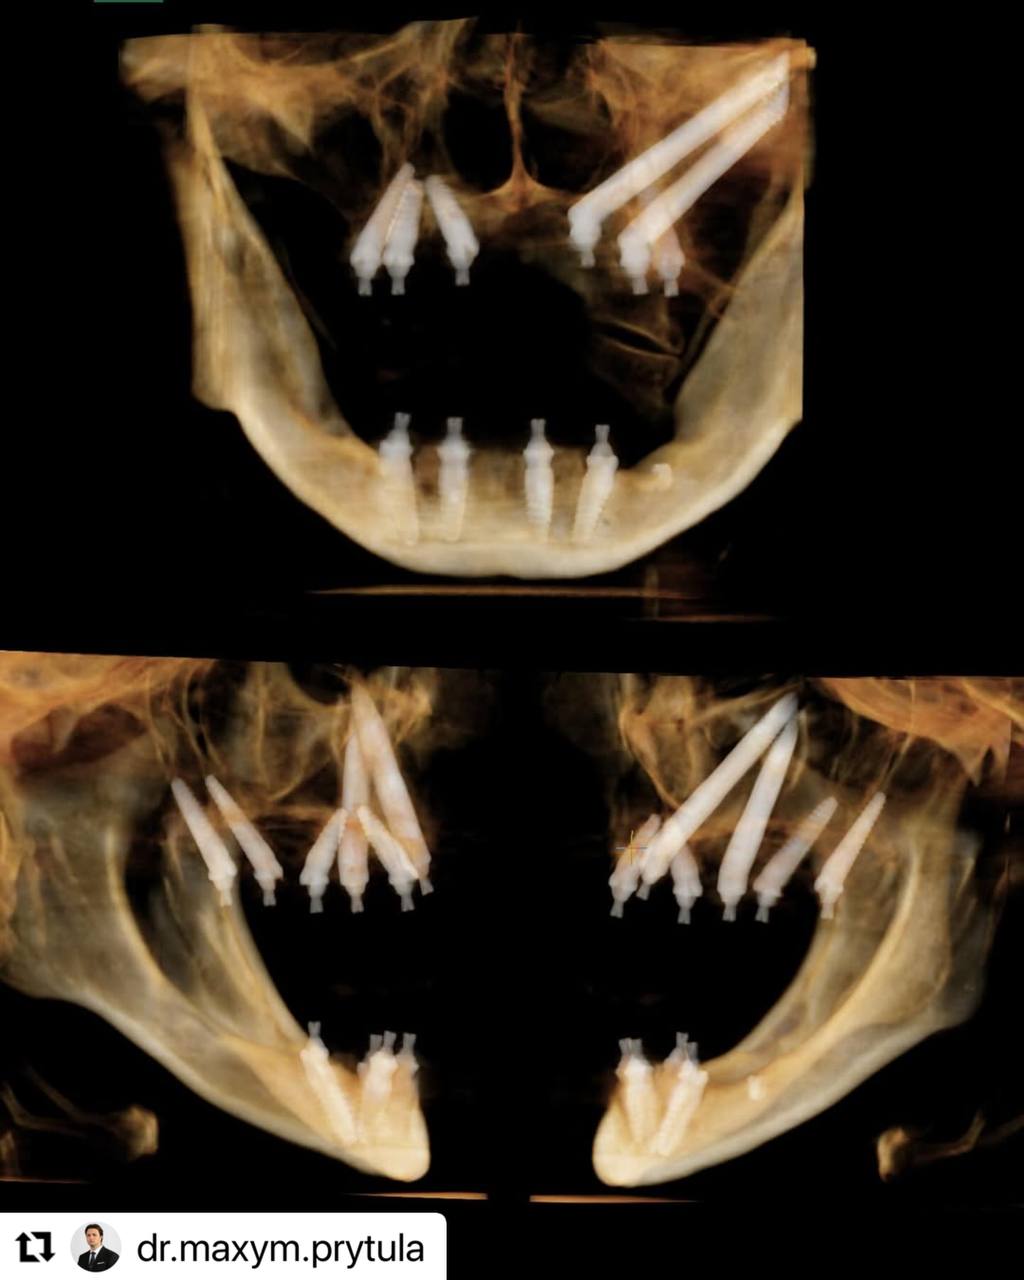

An interesting case illustrating the ability to combine different approaches and implant configurations depending on the atrophy of the maxilla.

Residual bone and anchorage points are a hot topic of discussion at the moment, due to different schools clashing on what approach is more stable: a 10- mm tilted palataly exposed implant or a 30+ mm zygomatic implant. In this specific clinical case we had the opportunity to properly utilise both techniques in respect to the indications for them.

The first sector while being both vertically and horizontally atrophied had enough bone proposition to place a 11.5mm anterior palatally-exposed implant into the canine pillar and a 13mm tilted implant in Zone2.

The second sector however did not have any residual bone whatsoever , including the absence of the Z-point hence the double-Zygoma configuration.

While I find anterior zygomatic implants a defective technique from a biomechanical perspective in comparison to conventional and trans-nasal implants it is important to note that no alternative was available in this specific situation.

In these scenarios anatomical precision is a key factor, that is why we tend to utilise guided surgery, mainly bone-supported guides, which allow us to confidently place implants and achieve high primary stability while at the same time providing an optimal restorative position to better distribute AP-spread. Overall, both approaches are effective and allow the patient to be loaded immediately and receive a final prosthesis in 3-4 months, however indications have to be respected.